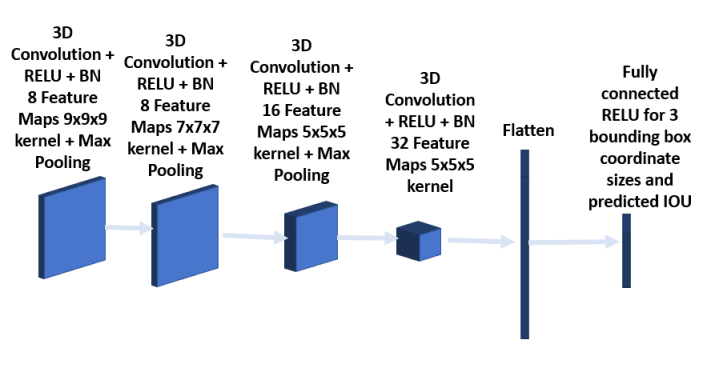

The bounding box network shown in Figure 6 is trained to predict the three coordinate sizes of the ROI. As the pre-selected bounding box is navigated, the regions whose IOUs exceed a threshold level are stored, along with ground truth sizes for training the bounding box network. The predicted IOU from the bounding box network is used as a confidence level associated with the bounding box. This feature is used in bounding box fusion (3.2.6) and also in semi supervised learning for pseudo label selection. The bounding box network consists of three 3D convolution layers together with batch normalization and RELU activation. The kernel size of the first, second and third convolution layers are 7x7x7, 5x5x5 and 3x3x3 respectively. The convolution layers are followed first by a fully connected layer and then by a RELU layer for 3 coordinate sizes. The loss function used is mean square error.

To improve overall performance, two other CNN architectures were trained besides the one described above, and the predicted bounding boxes using all three models are provided to the next stage for analysis. The architecture of the second model consists of 6 convolution layers as shown in Figures 7 and 8 respectively. The first 2 layers have kernel size 7x7x7, followed by 2 convolution layers with kernel size 5x5x5 and the final 2 convolution layers having kernel size 3x3x3. Each convolution layer is followed by batch normalization. Max pooling is added after the second and fourth layer. The third model as shown in Figures 9 and 10 has a convolution layer with 9x9x9 kernel and a batch normalization preceding the architecture in the model shown in Figures 5 and 6.